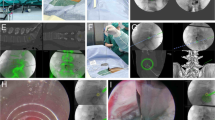

The procedure was performed under local anesthesia; one US doctor (a physician with more than 4 years of experience with interventional US and musculoskeletal US) held the probe, and one surgeon (an orthopedist with more than 5 years of experience with PELD) performed the puncture. The positions of the US doctor and surgeon and the positions of the US probe and surgeon’s hands during the puncture process are displayed in Fig. 1. In the control group, the same orthopedist performed the entire procedure independently.

Second, the puncture position was displayed. We found the transverse process and moved the probe upward, causing the soft tissue outside the intervertebral foramen to appear as a circular hyperechoic zone (HZ) after the disappearance of the superior margin of the transverse process, which is located below the facet joint (Fig. 2).

Ultrasound image and diagrammatic sketch of the lumbar and hyperechoic zones. aSP spinous process, FJ facet joint, HZ hyperechoic zone. The yellow arrow points to the HZ, which is the puncture target and is indicated by a yellow circle. The SP and FJ appear as hyperechogenicities on the ultrasound image. b The blue circle indicates the HZ, which is located under the FJ

Third, we drew an auxiliary line on the skin of the patient’s back at least 9–13 cm from the midline. We sterilized the skin with iodophor for better coupling with the probe. The HZ is located cephalad to the transverse process, which is located below the facet joint, and was used as the target. A needle was inserted from 12 to 3 o’clock (clockwise) of the HZ. The tip of the 18-gauge spinal needle first touched the facet joint and was then slipped inside the intervertebral foramen. G-arm X-ray (Whale, Massachusetts, United States) was used to test the needle position in the anteroposterior and lateral directions after confirming that the tip of the needle had been placed at the target point (Fig. 3).

Fourth, a guide wire was inserted through the spinal needle, and the spinal needle was removed. Then, a dilator was introduced along the guide wire. Finally, the endoscope outer sheath was inserted through the guide wire, and the position of the sheath was verified by G-arm X-ray (Fig. 4). Subsequently, transforaminal PELD was performed.